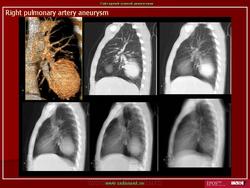

Аневризма легочной артерии.

Продолжение.